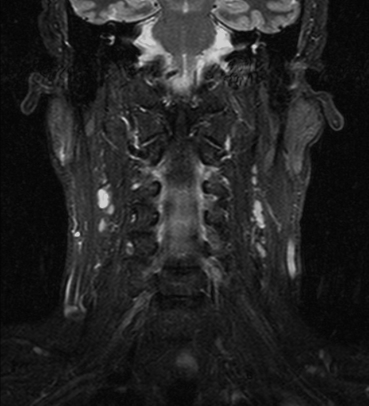

RM Partes Blandas

Prueba diagnóstica no invasiva que consiste en la obtención de imágenes de alta definición anatómica del cuello mediante el empleo de un campo electromagnético y ondas de radio (con un emisor y un receptor). No utiliza radiación ionizante. Indicaciones: sospecha de tumor, infecciones, ganglios.